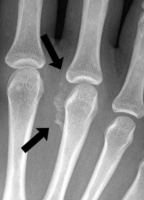

- plus rarement au niveau de la main, du poignet ou des doigts

* typiquement au niveau du fléchisseur ulnaire du carpe (cubital antérieur) proche du pisiforme

Aspect Radiologique : reflète la durée de la maladie

- stade de début,  les cristaux apparaissent mal définis et nuageux,

- avec la progression de la maladie, ils apparaissent plus denses et homogènes avec une configuration linéaire ou circulaire.